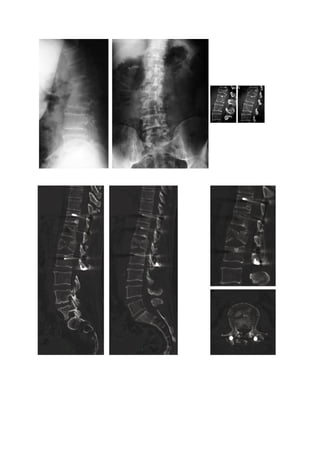

Patiente     de   21   ans.    Fracture   de     L1.    Absence   de    troubles   neurologiques.

Scanner           :         Fracture          de           L1         en         flexion.

Trait     passant     par     les     pédicules      de     L1    et     la    lame     de      L1.

Fracture                    type                     B2                    de                   L1.

Fracture à haut potentiel d’instabilité mais à instabilité “temporaire” (consolidation possible du

trait                                         de                                         fracture).

ART=16°

Pas                          de                          sténose                        canalaire.

Divers options : Traitement : Réduction et contention. Orthopédique, technique de Boehler.

Réduction et synthèse percutanée. Réduction synthèse à ciel ouvert sans libération ni greffe.

Postop immédiat : Choix de la synthèse percutanée. Après réduction en décubitus ventral et

manoeuvres                        externes                       de                     réduction.

Recul de 1 an : Consolidation de la fracture. Les deux niveaux synthésés peuvent être libérés

par l’ablation de matériel.